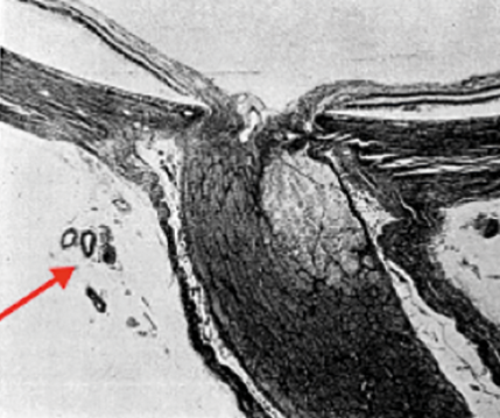

Figure 5: Top: (a) Retrolaminar infarct in the optic nerve with patent posterior arteries (arrowed) in NA-AION after Cogan. Bottom (b) Infarcted optic nerve head and retrolaminar infarction in AAION with occluded arteries from GCA (arrowed).

In contrast to the situation with the arteritic variety of AION, there is no convincing pathological report with associated clinical history of acute NA-AION. A specimen in Cogan’s book [9] shows a clear retrolaminar infarct in the presence of a patent posterior ciliary circulation (Figure 5a). The pathology of arteritic AION as shown in Figure 5b, in contrast, shows the infarcted ONH and retrolaminar ON with extensive inflammatory involvement of the posterior ciliary vessels by giant cell arteritis (GCA).